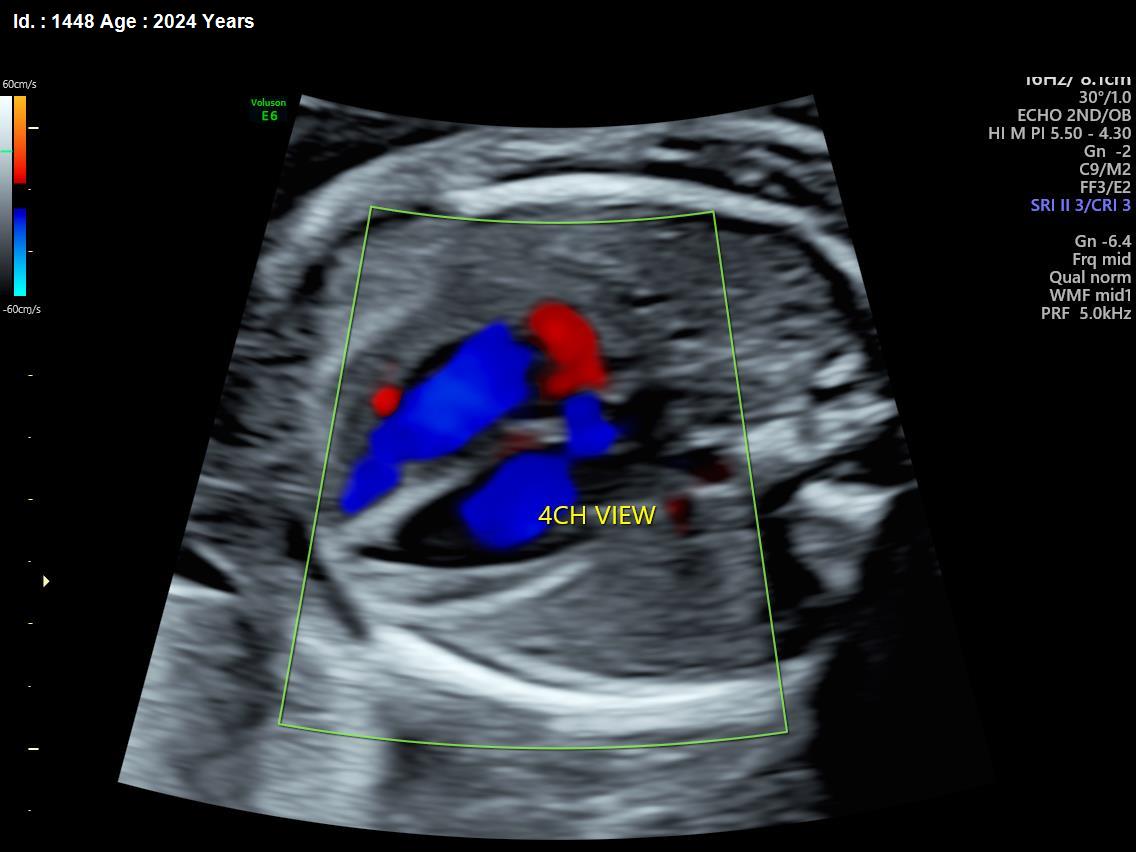

It is a test similar to ultrasound. It allows the doctor to see structure and function of the baby’s heart in detail. It also enables the doctor to see blood flow through fetal heart and cardiac rhythm. The scan is done by a radiologist or a fetal medicine specialist.

A fetal echocardiogram focuses specifically on the fetal heart, providing a detailed examination of its structure and function. In contrast, a standard ultrasound assesses overall fetal development and growth.